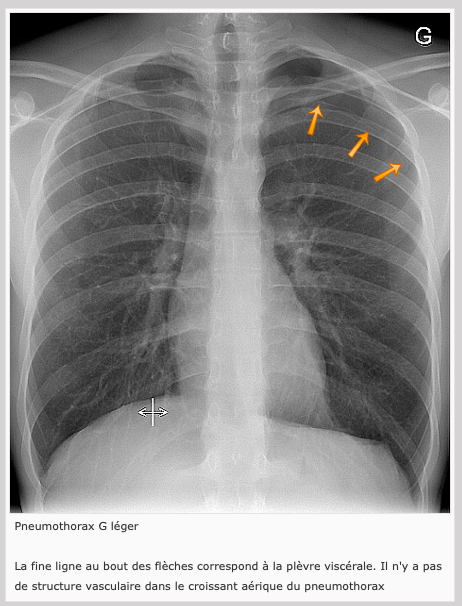

Pneumothorax

**Air s’accumule d’abord dans l’apex pulmonaire donc important de bien regarder là

Décollement pleural (pneumothorax)